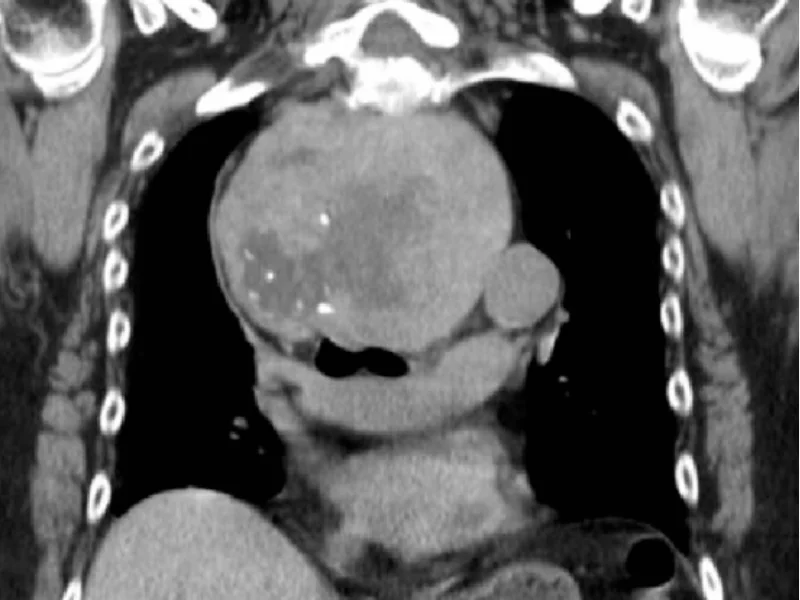

O bócio mergulhante é aquele que cresce para dentro do tórax, passando por baixo do esterno. Nesses casos:

- A compressão traqueal tende a ser mais intensa

- Não é possível acompanhar o crescimento apenas pelo pescoço

- A cirurgia é tecnicamente mais complexa, mas continua sendo feita por acesso cervical (pelo pescoço) na maioria dos casos

- Adiar aumenta o risco de complicações respiratórias

Se o seu ultrassom ou tomografia mostrou extensão intratorácica, a avaliação cirúrgica deve ser prioritária.